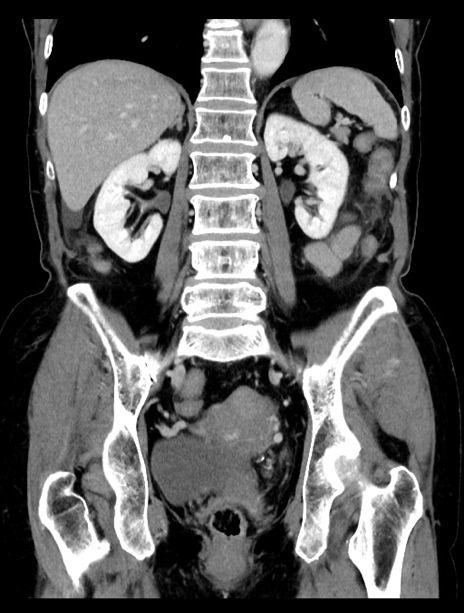

症例23(冠状断像)

【症例】70歳代女性

【主訴】下腹部痛・嘔吐

【現病歴】2日前より腹痛あり。昨日嘔吐あり。症状改善しないため来院。

【既往歴】胃GISTに対して胃部分切除後。

【身体所見】BT 37.1℃、BP 128/77mmHg、腹部:平坦・軟、下腹部に圧痛あり。

【データ】WBC 10200、CRP 0.31